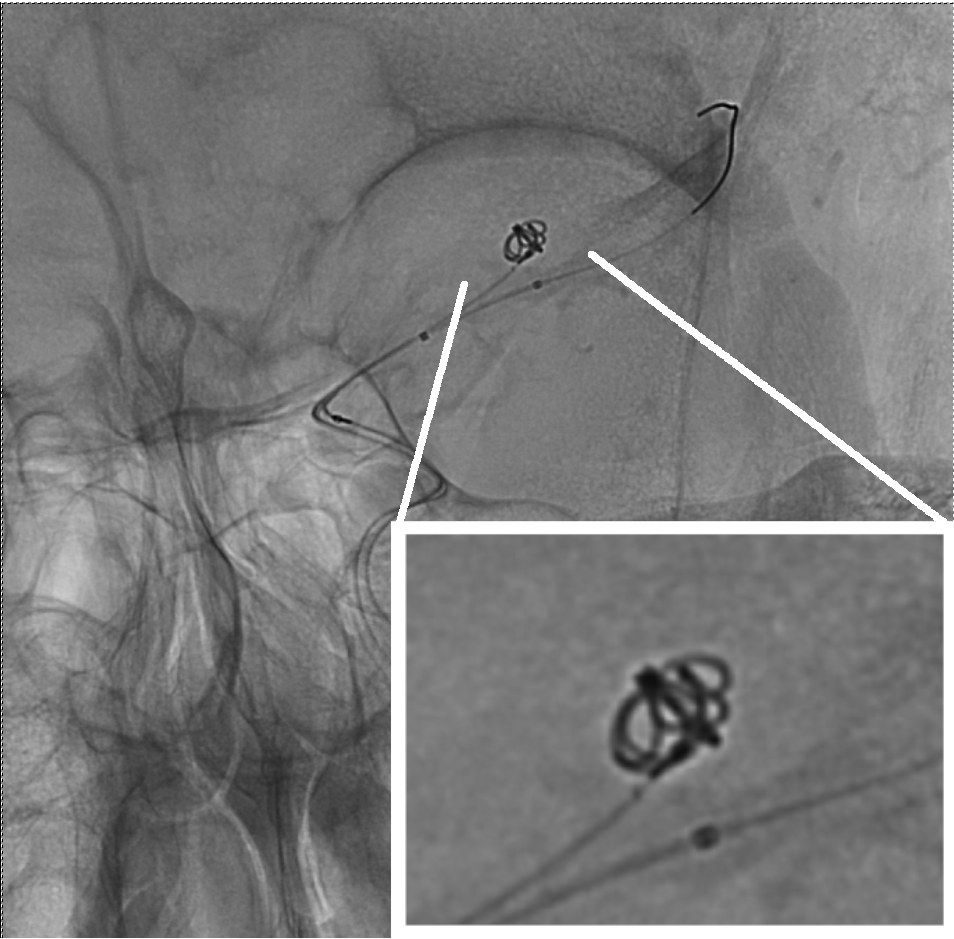

Angiogram during coil embolization. The framing coil was inserted to Aneurysm Framing Coils endovascular coil embolisation continues to evolve and remains a valid modality in managing. the importance of a framing coil (fc)—the first coil inserted into an aneurysm during endovascular coiling, also called a lead. the framing coil’s role as the initial barrier to aneurysm sac inflow is critical when further coils are introduced,. framing strategies for oblong. Aneurysm Framing Coils.

Coiling of an aneurysm of the PPTAICA junction. (A) CTA showing a

Coiling of an aneurysm of the PPTAICA junction. (A) CTA showing a Aneurysm Framing Coils the framing coil’s role as the initial barrier to aneurysm sac inflow is critical when further coils are introduced,. endovascular coil embolisation continues to evolve and remains a valid modality in managing. framing strategies for oblong aneurysms may involve coils that are. the importance of a framing coil (fc)—the first coil inserted into an aneurysm during. Aneurysm Framing Coils.

A Angiographic image of distal ICA aneurysm. B Frame coil formed Aneurysm Framing Coils framing strategies for oblong aneurysms may involve coils that are. endovascular coil embolisation continues to evolve and remains a valid modality in managing. the framing coil’s role as the initial barrier to aneurysm sac inflow is critical when further coils are introduced,. the importance of a framing coil (fc)—the first coil inserted into an aneurysm during. Aneurysm Framing Coils.